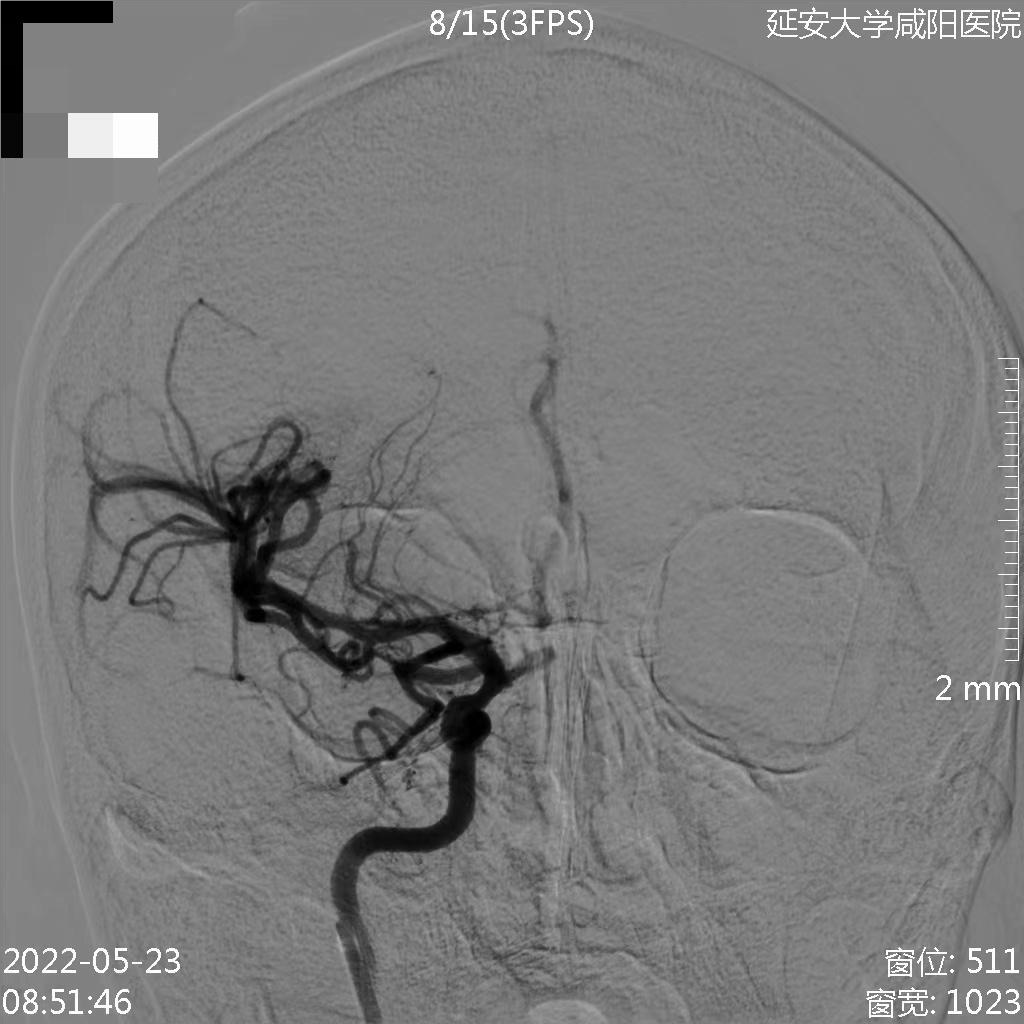

第三节

右侧颈内动脉起始部急性闭塞并右侧大脑中动脉急性血栓

来自延安大学咸阳医院的王琨教授分享了一例右侧颈内动脉急性闭塞并大脑中动脉血栓的病例。

术前检查

病历夹什么径技·第152期|串联营病历夹:川陕大营_https://www.jmylbn.com_新闻资讯_第59张

病历夹什么径技·第152期|串联营病历夹:川陕大营_https://www.jmylbn.com_新闻资讯_第60张

病历夹什么径技·第152期|串联营病历夹:川陕大营_https://www.jmylbn.com_新闻资讯_第61张

<<滑动查看下一张图片>>

初步诊断:1.脑梗死(右)急性期2.右侧颈内动脉起始部次全闭塞3.右侧大脑中动脉M1段血栓形成